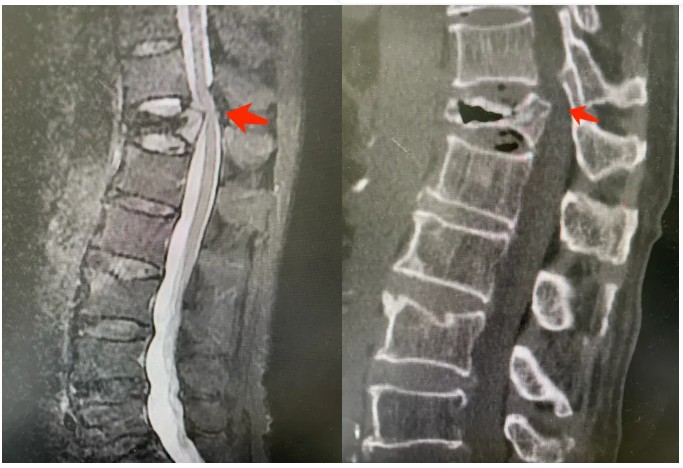

来到徐州一院就诊后,经影像学检查发现,李先生为胸12椎体陈旧性骨折并发Kummell病,椎体内部出现坏死和塌陷,并对脊髓神经造成压迫。

术前检查显示骨折未愈合,压迫脊髓神经